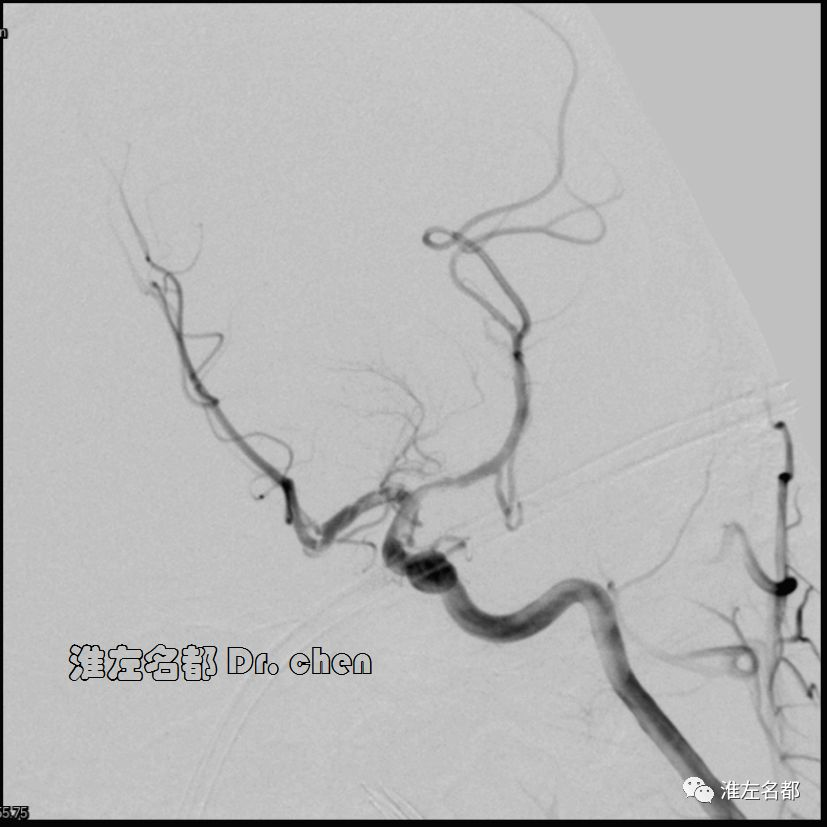

△经.035”泥鳅导丝将中间导管(Navien 058,125cm)送至左侧颈内动脉岩骨段,而后长鞘跟进至左侧颈内动脉,再经泥鳅导丝将中间导管送至海绵窦段,微导管(Rebar 27)在微导丝导引下进入左侧大脑中动脉M2段,造影证实位于真腔后,经微导管释放取栓支架(S AB 6*30mm)后造影:左侧颈内动脉远端充盈缺损,管腔严重狭窄;左侧大脑中动脉近端严重狭窄。

3.脑动脉夹层临床确诊依赖于影像学检测到典型夹层征象:内膜征/双腔征、长段不规则/丝线样狭窄、壁内血肿、夹层动脉瘤等。本患儿DSA显示左侧颈内动脉末端和大脑中动脉主干长段狭窄,且大脑中动脉主干狭窄呈“丝线样”,符合夹层影像学征象。

4.文献罕有报道颅内动脉夹层闭塞所致脑卒中急诊血管治疗案例,具体治疗策略也不明确。在本病例,应用S AB 6*30mm支架结合中间导管,以中间导管逆向回收的SWIM技术成功开通夹层所致的颅内前循环极重度狭窄。笔者使用上述技术是基于以下考虑:

5.术中,取栓支架仅取出小块血栓,推测取栓支架压迫和中间导管逆向回收支架时按压假腔是夹层真腔得以恢复的主要原因。